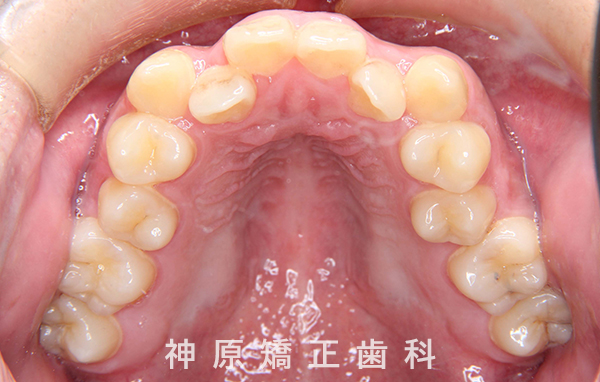

初診時